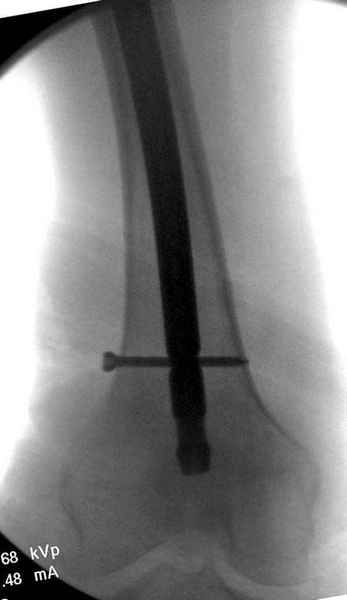

Правильно, ситуация изменилась, как говорят у нас теперь "different animal", надо решать проблему подвертельного перелома. При наличии различных вариантов фиксаторов, включая Страйкер Гамма 3, мы выбрали DePuy Antegrade Trachanteric Nail из-за многовариантности проксимальной фиксации и двойного изгиба. Вводится через вертел под 8 градусным углом, и есть достаточный передний диафизарный изгиб, предупреждающий пенетрацию дистального переднего кортекса.